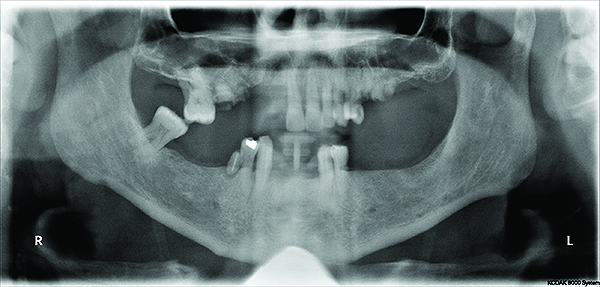

A 58-year-old male presented in reasonably good general health. No contraindications to providing dental care were discovered. He was referred for evaluation for full mouth extraction and subsequent placement of a full upper denture and implant-retained lower denture. Intraoral examination revealed a failing dentition with loss of posterior supporting teeth and flared, supra-erupted anterior teeth; panoramic radiograph confirmed the failing dentition diagnosis. The patient exhibited a deep overbite and excessive overjet (Figure 1 through Figure 4). Upon interview, the patient approved the treatment for which he was referred. No intraoral contraindications to treatment were encountered. The treatment plan consisted of two distinct phases. A first phase of treatment was suggested to transition the patient from failing dentition to treatment dentures. A second phase of treatment six months later was recommended to provide definitive treatment. This plan would include implant treatment to stabilize the mandibular appliance.

Fig 4. Preoperative panoramic radiograph revealing the failing dentition.

Figure 4